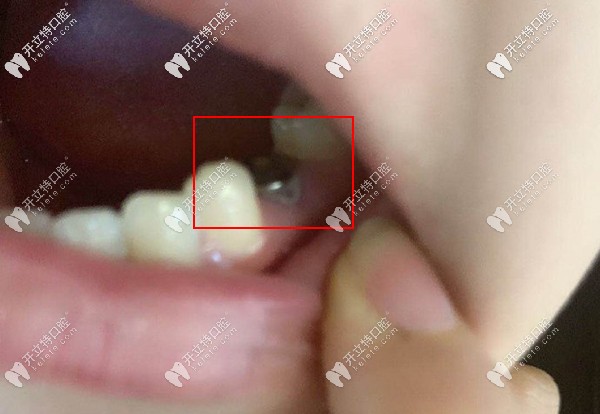

下前磨牙齲壞

本來(lái)小姐姐沒想著要做種植牙,但是吃飯老是塞東西,牙齒容易發(fā)炎。然后來(lái)醫(yī)院咨詢自己適合做什么種植體,考慮到她年輕,牙槽骨條件比較好,醫(yī)生推薦的韓國(guó)進(jìn)口種植體,價(jià)格不算貴,種植成功率還高。

這是她給拍的缺牙處種上了種植體

缺牙處種上了種植體